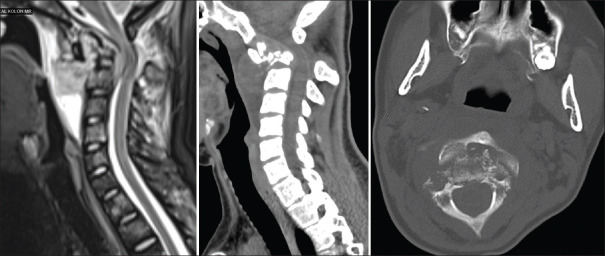

枕颈交界处(OCJ)是一个复杂的解剖区域,对保护下脑干、上脊髓和下颅神经至关重要。该区域的不稳定性可导致慢性疼痛、神经功能缺损或死亡等严重后果。目前已开发出多种用于稳定 OCJ 的手术技术,尤其是使用枕骨髁螺钉,这些技术在提供稳定性和保持颈部旋转方面已显示出良好的前景。本文介绍了两例因C2椎体转移性受累而导致的OCJ不稳定病例,这两例病例均采用枕骨髁螺钉固定术成功治愈。第一例患者是一名 22 岁的女性,患有尤文肉瘤转移;第二例患者是一名 62 岁的男性,患有多发性骨髓瘤。两名患者术后的神经功能和颈椎稳定性均有明显改善,并可观察到穴位重塑。我们的研究结果表明,枕骨髁螺钉固定术不仅可行,而且能有效治疗转移性疾病导致的 OCJ 不稳定。详细的术前评估和使用先进的术中成像技术(如 O 型臂和神经导航)对于最大限度地提高安全性和确保最佳治疗效果至关重要。这项研究强调了枕骨髁螺钉固定术作为一种主要手术方法在适当病例中稳定 OCJ 的潜力。

The occipitocervical junction (OCJ) is a complex anatomical region crucial for protecting the lower brain stem, upper spinal cord, and lower cranial nerves. Instability in this area can lead to severe outcomes such as chronic pain, neurological deficits, or death. Various surgical techniques have been developed for OCJ stabilization, particularly using occipital condyle screws, which have shown promise in providing stability and preserving neck rotation. This article presents two cases of OCJ instability caused by metastatic involvement of the C2 vertebra, managed successfully with occipital condyle screw fixation. The first case involved a 22-year-old female with Ewing sarcoma metastasis, and the second case involved a 62-year-old male with multiple myeloma. Both patients exhibited significant improvements in neurological function and cervical stability postoperatively, with observable den remodeling. Our findings suggest that occipital condyle screw fixation is not only feasible but also effective in managing OCJ instability due to metastatic disease. Detailed preoperative evaluation and the use of advanced intraoperative imaging technologies, such as the O-arm and neuronavigation, are essential for maximizing safety and ensuring optimal outcomes. This study underscores the potential of occipital condyle screw fixation as a primary surgical method for stabilizing the OCJ in appropriate cases.